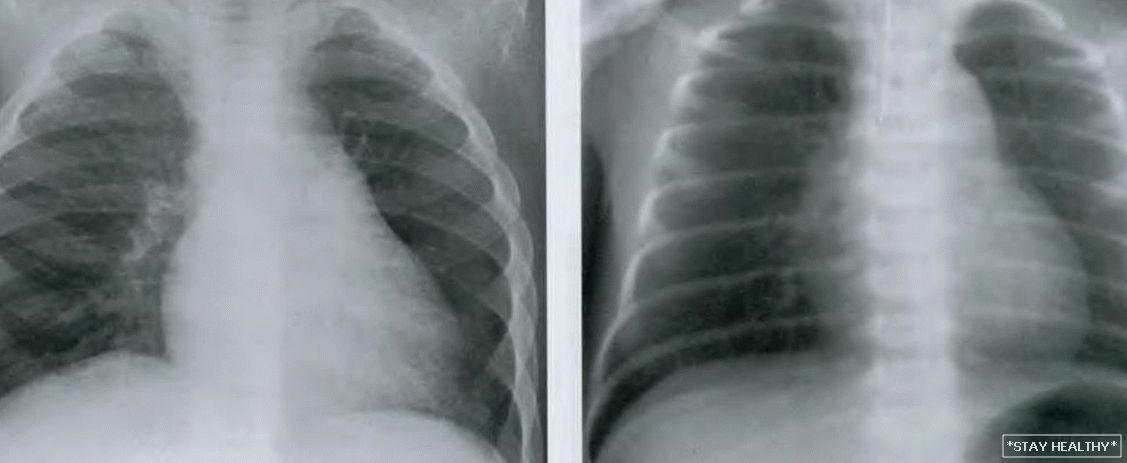

Нормальная рентгенограмма легких: что нужно знать

Раздел: Мудрость в объективе